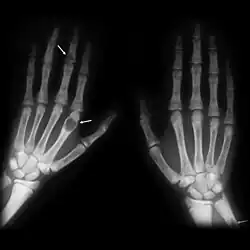

Brown tumours of the hands in a patient with hyperparathyroidism.

The brown tumor is a bone lesion that arises in settings of excess osteoclast activity, such as hyperparathyroidism. They are a form of osteitis fibrosa cystica. It is not a neoplasm, but rather simply a mass. It most commonly affects the maxilla and mandible, though any bone may be affected.[1] Brown tumours are radiolucent on x-ray.

Radiographically, brown tumor may show no detectable changes or a generalized osteoporosis. Partial loss of lamina dura around the teeth may occur but is not a constant feature. Focal Lesions (Brown Tumor) present as sharply defined, round or oval radiolucent areas which may appear multilocular. Such lesions occur more frequently in mandible than maxilla [6]